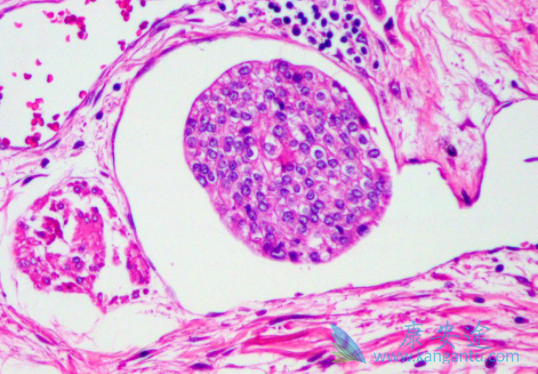

为明确拉帕替尼(Tykerb)维持治疗用于人类表皮生长因子受体(HER)1 / HER2阳性的一线化疗后转移性膀胱尿路上皮癌(UBC)是否有获益。一项III期双盲随机临床试验拟入组的转移性UBC患者的组织样本在中心实验室进行HER1 / HER2有过表达检测。符合入组条件的HER1/2表达阳性转移性UBC患者接受四至八个周期的化疗。

化疗疗效评估为无进展性的患者随机分配至拉帕替尼维持治疗组或安慰剂对照组。研究共入组了446例UBC患者,其中232例HER1-或HER2阳性患者被随机分配到试验组及对照组。拉帕替尼组和安慰剂组的中位PFS分别为4.5个月和5.1个月。拉帕替尼组和安慰剂组的总生存期分别为12.6个月和12.0个月。两组中因不良事件导致试验终止的发生率相似(拉帕替尼组6%和安慰剂组5%)。

拉帕替尼(Tykerb)组和安慰剂组的3-4级不良事件的发生率分别为8.6%和8.1%。对HER1 / HER2均强阳性的患者,HER1单阳性的患者(n= 102)和HER2单阳性的患者(n = 42)进行预先计划的亚组分析,结果显示在PFS和总生存期方面,拉帕替尼维持治疗组没有显着获益。结论:该试验未能证明标准治疗中加入拉帕替尼维持治疗能显着改善结局。